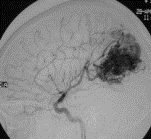

7、選擇性全腦血管造影(DSA)可了解AVM的部位、供血動脈、畸形血管團大小以及引流靜脈,了解是否伴有動脈瘤、靜脈瘤、動靜脈瘺及腦盜血情況。必要時加做頸外動脈造影,以了解是否有頸外動脈參與供血。

⑥腦血管造影。是診斷動靜脈畸形的重要手段。是必須進行的檢查方法。不僅能確定診斷而且還為治療提供依據。造影常顯示不規則曲張扭纏的畸形血管團,並可顯示供血動脈和引流靜脈。引流靜脈常在動脈期即可過早顯影。但仍有一部分小的或隱匿型動靜脈畸形不能被造影發現(約11%)。數字減影、放大造影、連續攝片、立體血管造影等更有助於診斷。